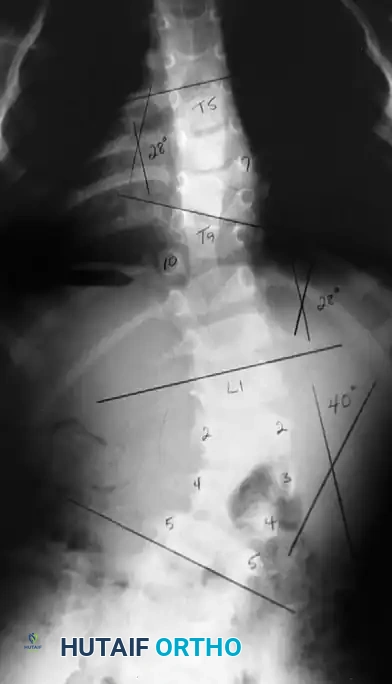

Image

Surgical planning and execution of complex congenital curve corrections.